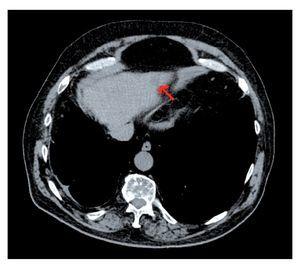

Al cabo de tres años de seguimiento, se detectó mediante TC una lesión sólida hipodensa de 1.5 cm de localización periférica en segmento II confirmada mediante resonancia magnética (RM) compatible con recidiva tumoral (Figura 3).

¿ Figura 3. TC abdominopélvica: lesión hipodensa de 1.5 cm en segmento II hepático (flecha) .